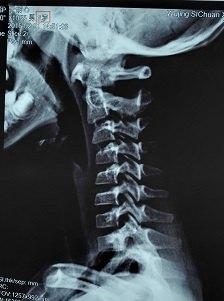

颈椎曲度变直或反弓是骨科临床常见的影像表现,随着生活方式的改变,其出现年龄逐年减小,目前为止,笔者所见病例中,最小年龄为6岁!该患者主因颈痛,头部昏重,恶心欲吐来门诊就诊。如下图X片即为该6岁患儿的片子。

6岁患儿的颈椎X片